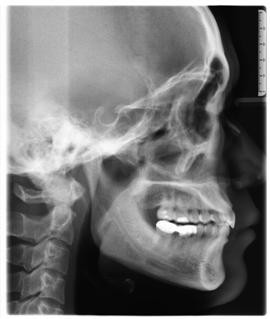

临床诊断:通过数字化全景机的检查,患者的上牙前突属于牙性,双唇闭合时可见明显隆起,X片显示根尖无异常,上下后牙存在间隙,可通过美国MBT直弓丝正畸技术将其矫正复位,并收拢间隙,矫正所需时间一年半左右。